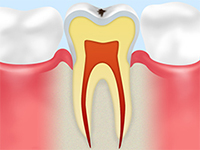

虫歯の進行状態と治療法

虫歯の進行度合いにはCO~C4の5段階があり、それぞれに特有の症状が現れます。また治療内容も各段階で異なります。

C3

| 症状 |

| 血管や神経が集まる部分にまで虫歯が達し、何もしなくてもズキズキとした痛みを感じるようになります。 |

| 治療 |

| 冒された神経などを除去し、そこに薬剤を注入して詰め物をする「根管治療」が必要です。 |